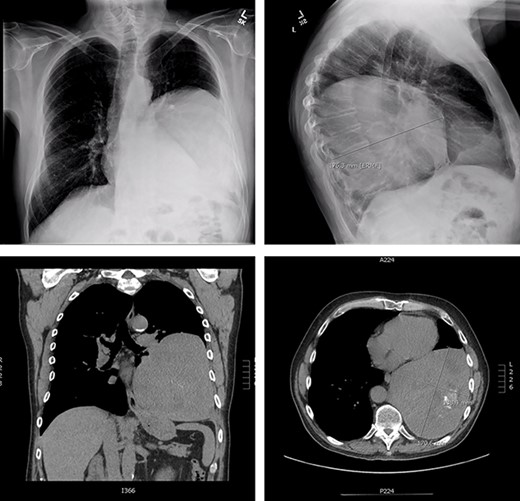

The patient is a 70-year-old man with a 75-pack-year smoking history and occupational asbestos exposure, who presented with back pain and constitutional symptoms in 2019. Physical exam was unremarkable except for hypertrophic pulmonary osteoarthropathy with digital clubbing. Computed tomography chest demonstrated a 18.3 × 17.0 × 13.8 cm left pleural-based tumour, with heterogeneous density and internal calcifications, resulting in compression of the left lower bronchi (Fig. 1). The patient’s medical records revealed that he was originally diagnosed with a left-side pleural SFT in 2013 (Fig. 2); imaging and biopsy at that time revealed a 9.3 cm spindle cell tumour consistent with SFT. The patient was lost to follow-up.

Representation of solitary fibrous tumour in 2019 showing 18.3 × 17.0 × 13.8 cm left-sided pleural-based tumour.